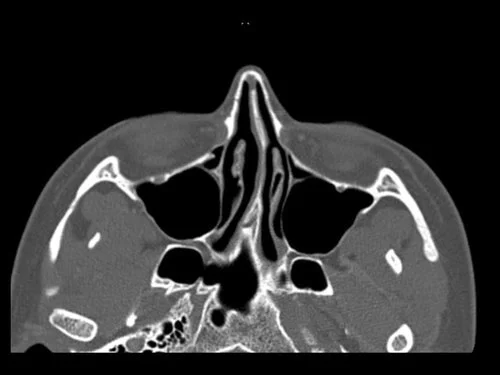

Septoplasty is a surgical procedure that is used to straighten a deviated septum. The nasal septum separates the two nasal cavities. The nasal septum may be deviated because you were born with a cooked septum or it grew into a crooked shape. A deviated septum can restrict the flow of air through your nose making it difficult to breath.

Depending on the shape of the septum, you may experience breathing difficulty on one or both sides of your nose. Some degree of septal deviation occurs in almost everyone. Reasons why more severe septal deviation can occur are related to abnormal growth, trauma or previous surgery. Symptoms such as difficulty breathing through the nose or intense snoring may indicate the need for a septoplasty. Deviation of the nasal septum frequently gives the nose a C-shape or crooked appearance, but occasionally the nose may appear straight while the septum deeper in the nose is deviated.

• During a septoplasty, Dr. Derderian removes abnormally curved bone and cartilage from the septum. He then repositions the nasal septum to the midline while using grafts from the removed portion of the septum to maintain the new straightened shape. He is usually able to work through incisions inside the nose, but it is occasionally necessary to make a small incision between the nostrils. Depending on the shape of the nasal bones, it may also be necessary to break the nasal bones so they can be repositioned. Repositioning of the nasal bones is very common in septoplasty performed to correct a crooked nose and deviated nasal septum due to trauma. Soft silicone splints are commonly placed in the nose after surgery to support the septum in its new position.